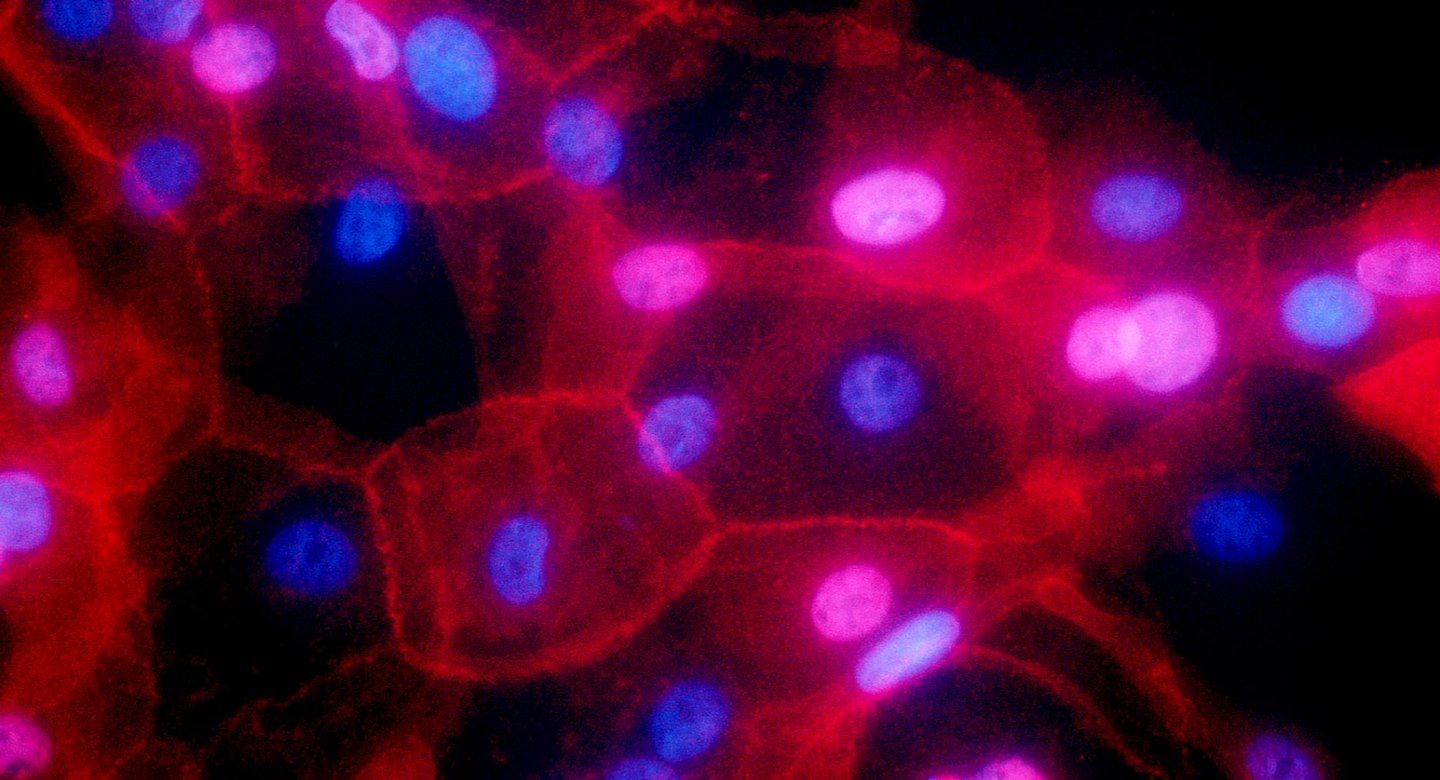

Researchers at UC San Francisco and UC San Diego have mapped out how hundreds of mutations involved in two types of cancer affect the activity of proteins that are the ultimate actors behind the disease. The work points the way to identifying new precision treatments that may avoid the side effects common with much current chemotherapy.

The team’s new studies describe the approach in detail, and highlight findings when it was applied to breast cancer and cancers of the head and neck.

There is a subset of genes that are commonly mutated in cancer, and each of these genes can be mutated in hundreds of different ways, said Krogan, who is also a senior investigator at Gladstone Institutes. In addition, the function of a particular protein may be different in different types of cells, so a mutation in a breast cancer cell might have different effects on protein complexes than that same mutation’s effect in a cell of the throat.

CCMI’s goal was to map the constellation of protein complexes formed by about 60 genes commonly involved in either breast cancer or cancers of the head and neck, and to see what each looked like in healthy cells. Alongside that effort, he created maps of how protein complexes are affected by hundreds of gene mutations in two cancerous cell lines.